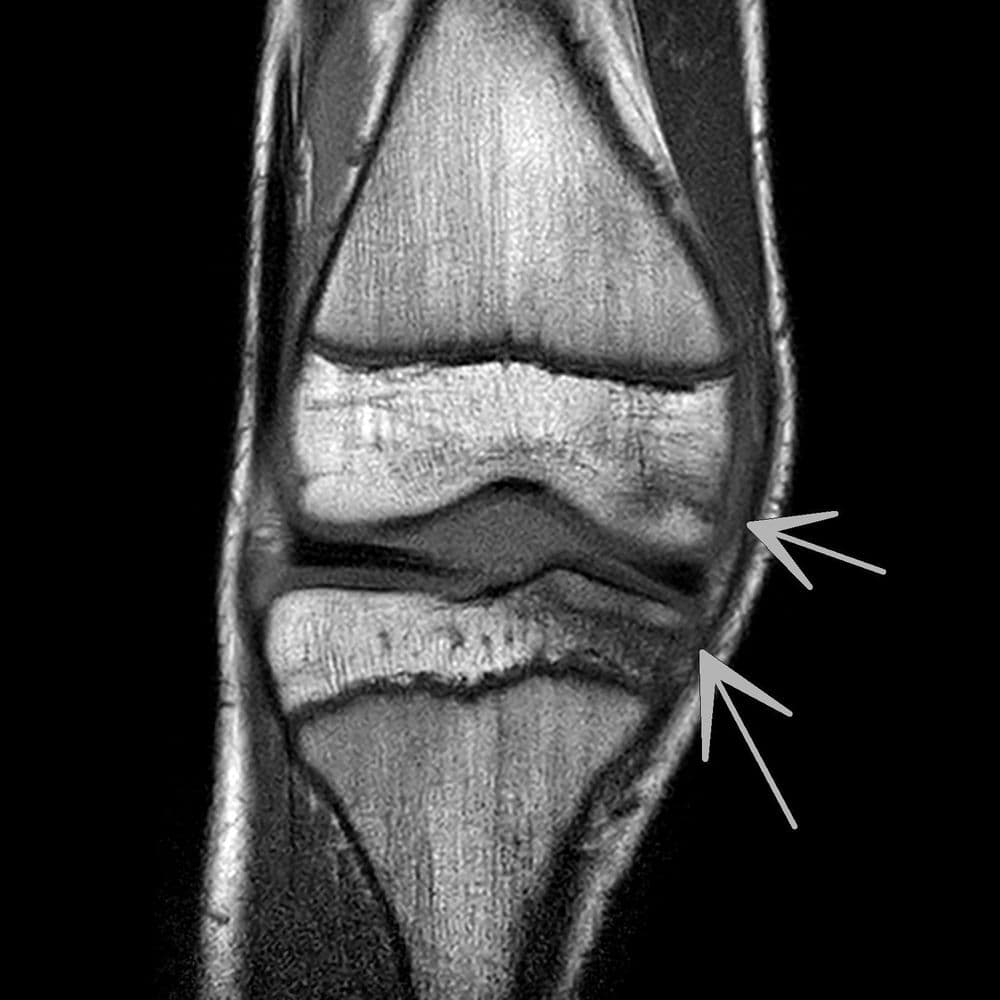

Désinsertion capsulo méniscale latérale chez un jeune sportif de 17 ans.

CT